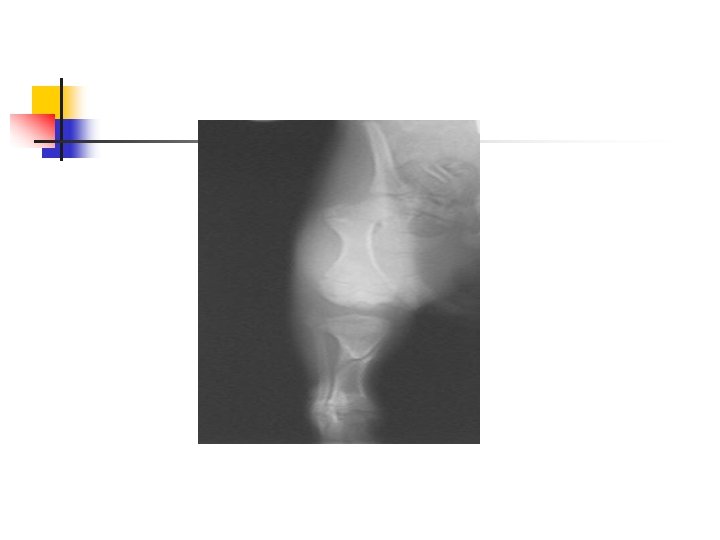

Stifle Joint n Caudocranial View n n n Positioned in sternal recumbency with affected limb pulled into position of maximum extension. Opposite limb may be elevated to help control the lateral rotation of the stifle joint under examination. May also do craniocaudal view.

Stifle n Lateral View n n Patient is placed in lateral recumbency with affected joint placed and centered on the cassette. Stifle joint should be in a natural, slightly flexed position.